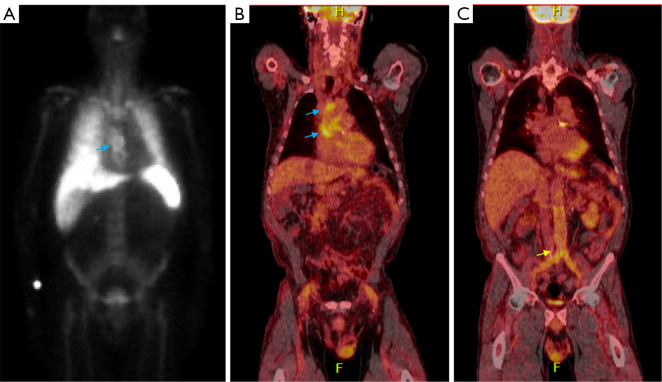

背景和目的:最近主要的国际社会指南强调了多模态成像在感染性心内膜炎(IE)评估中的应用。本文旨在通过实际案例讨论多模态成像在IE中的当代应用,展示如何使用新兴的成像方式,包括心脏计算机断层扫描(CCT)和核成像技术。方法:检索PubMed数据库2024年01月01日至2024年10月01日的文献。我们的综述使用了有关“感染性心内膜炎”和“多模态成像”的相关文章。从克利夫兰诊所基金会的四个临床病例被纳入补充这一文献综述与现实世界的例子。主要内容和发现:本文献综述包括国际心脏病学指南、调查研究、荟萃分析和专门的综述,重点介绍了不同成像方式在IE评估中的具体作用、优势和劣势,包括经胸和经食管超声心动图(TEE)、CCT、18f -氟脱氧葡萄糖正电子发射断层扫描(18F-FDG PET)和白细胞单光子发射计算机断层扫描(WBC SPECT)。这篇综述表明,鉴于越来越复杂的患者群体和越来越多的假体瓣膜和装置,这些多模态成像工具的新兴作用。结论:本文结合复杂的临床病例,讨论了目前的文献和指南,目的是说明多模态心脏成像在IE中的相对优势和劣势,以及适当的应用。

Background and objective: Recent major international society guidelines have highlighted the utility of multi-modality imaging in the evaluation of infective endocarditis (IE). This article aims to discuss the contemporary applications of multimodality imaging in IE through real-life cases, demonstrating how emerging imaging modalities, including cardiac computed tomography (CCT) and nuclear imaging techniques can be used.

Key content and findings: This literature review encompasses international cardiology guidelines, as well as investigational studies, meta-analyses, and dedicated reviews highlighting the specific roles, strengths, and weaknesses of different imaging modalities in the evaluation of IE, including transthoracic and transesophageal echocardiography (TEE), CCT, 18F-fluorodeoxyglucose positron emission tomography (18F-FDG PET), and white blood cell single-photon emission computed tomography (WBC SPECT). This review demonstrates the emerging role for these multi-modality imaging tools in light of an increasingly complex patient population with growing numbers of prosthetic valves and devices.